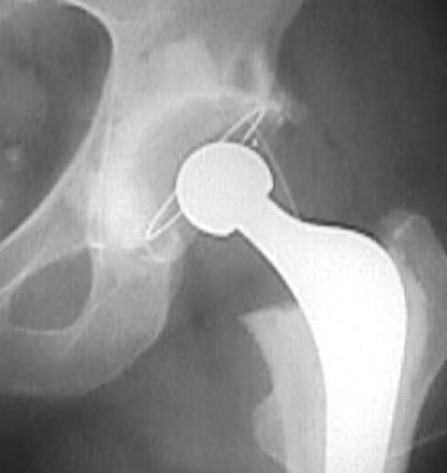

Inferior cement Inferior cement Intra-pelvic cement

Loosening

Signs

- obvious migration in comparison previous films

- cement mantle fracture

- progressive > 2 mm lucency

Charnley zones

1 - superior 1/3

2 - middle 1/3

3 - inferior 1/3